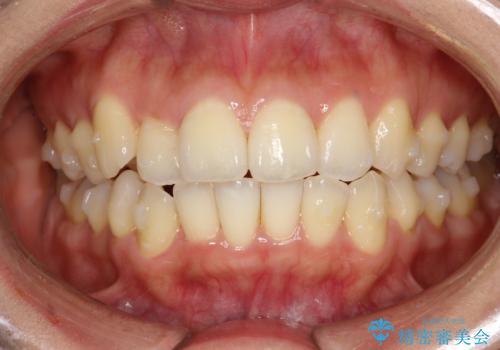

前歯が前後反対にかんでいる インビザラインによる目立たない矯正

- 前歯のかみ合わせを主訴に来院されました。

なるべく目立たずに矯正をしたいとのことで、インビザラインで矯正をすることとしました。

歯と歯の間をわずかに削り、ガタガタを改善しました。

目立たずに矯正を終えることができて、喜んでいただけました。